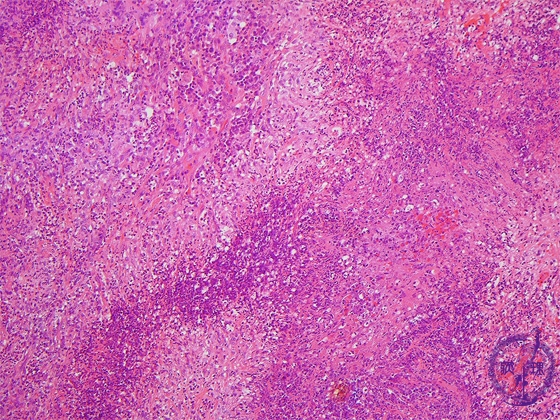

Microscopic view (low power view): The typical histological finding is a necrotizing vasculitis with necrotic granulomatosis. Geographic necrosis, comprising necrotic basophilic tissue and neutrophils, is remarkable in this case which also shows marked inflammation.